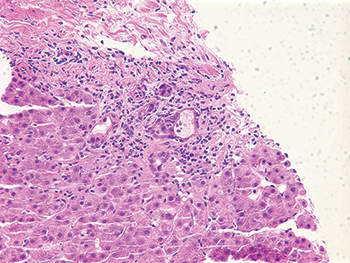

The effect of drugs on the liver can imitate many different patterns of liver injury, including hepatitic, vascular, and cholestatic, among others, said Dr. Najarian, a consultant in gastrointestinal, hepatobiliary, and pancreatic pathology at Beth Israel Deaconess Medical Center and Harvard Medical School. He described the image of an amoxicillin-clavulanic acid (Augmentin)-induced liver injury as essentially simulating a cholestatic pattern with bile ductular proliferation, portal tract edema, and neutrophils. “You could easily call this duct obstruction, if you didn’t know better that a patient had started a new drug recently,” he said (Fig. 1).